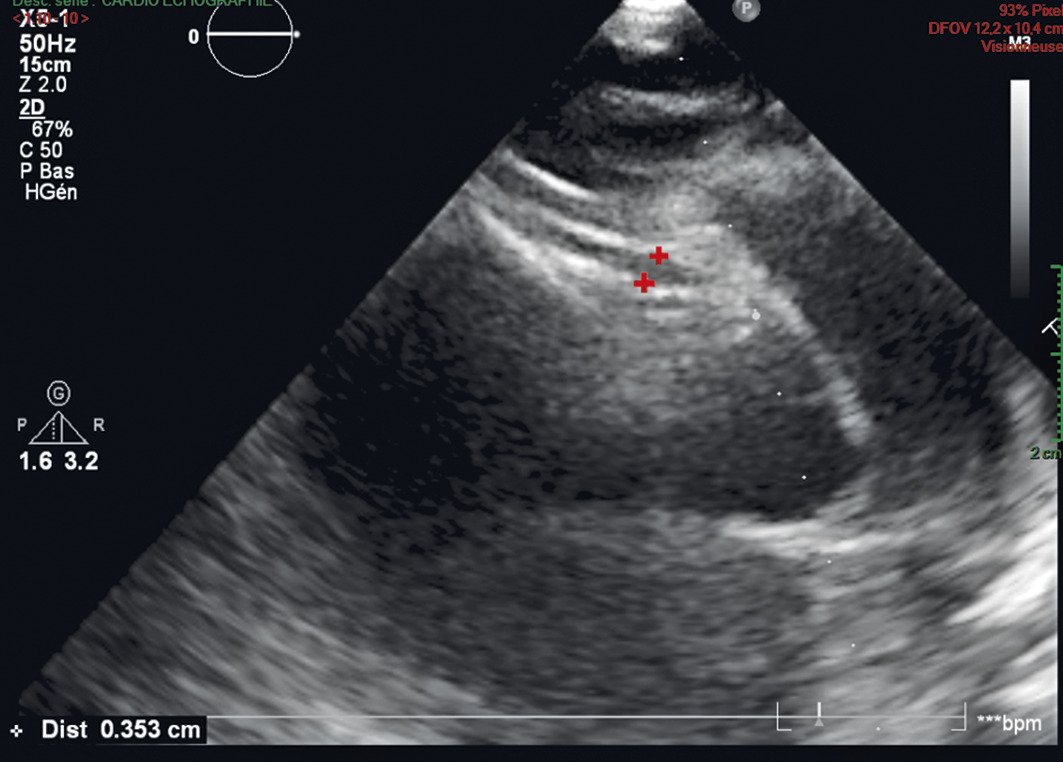

La maladie de Kawasaki est évoquée (forme complète). L’échographie cardiaque retrouve une dilatation modérée de l’artère coronaire droite (fig. 2 ). La perfusion d’immunoglobulines IV s’accompagne d’un retour à l’apyrexie dans les 72 heures.

La maladie de Kawasaki est évoquée (forme complète). L’échographie cardiaque retrouve une dilatation modérée de l’artère coronaire droite (